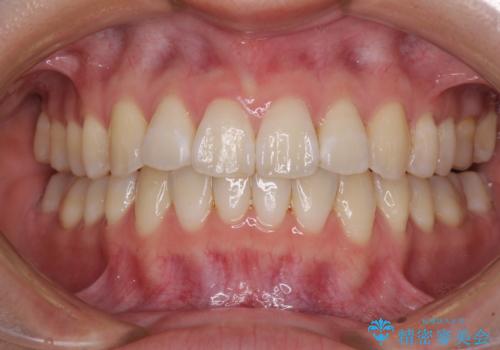

矯正治療の後戻り ガタガタになった前歯の部分矯正

- 以前の矯正治療の後戻りを気にして来院された患者様です。

下顎前歯にデコボコがあるため、ワイヤー矯正により改善することとしました。

もう少しデコボコを改善したかったのですが、ご本人の希望もあり、装置を除去しました。

後戻りを防止するため、舌側を細いワイヤーによる保定を行いました。